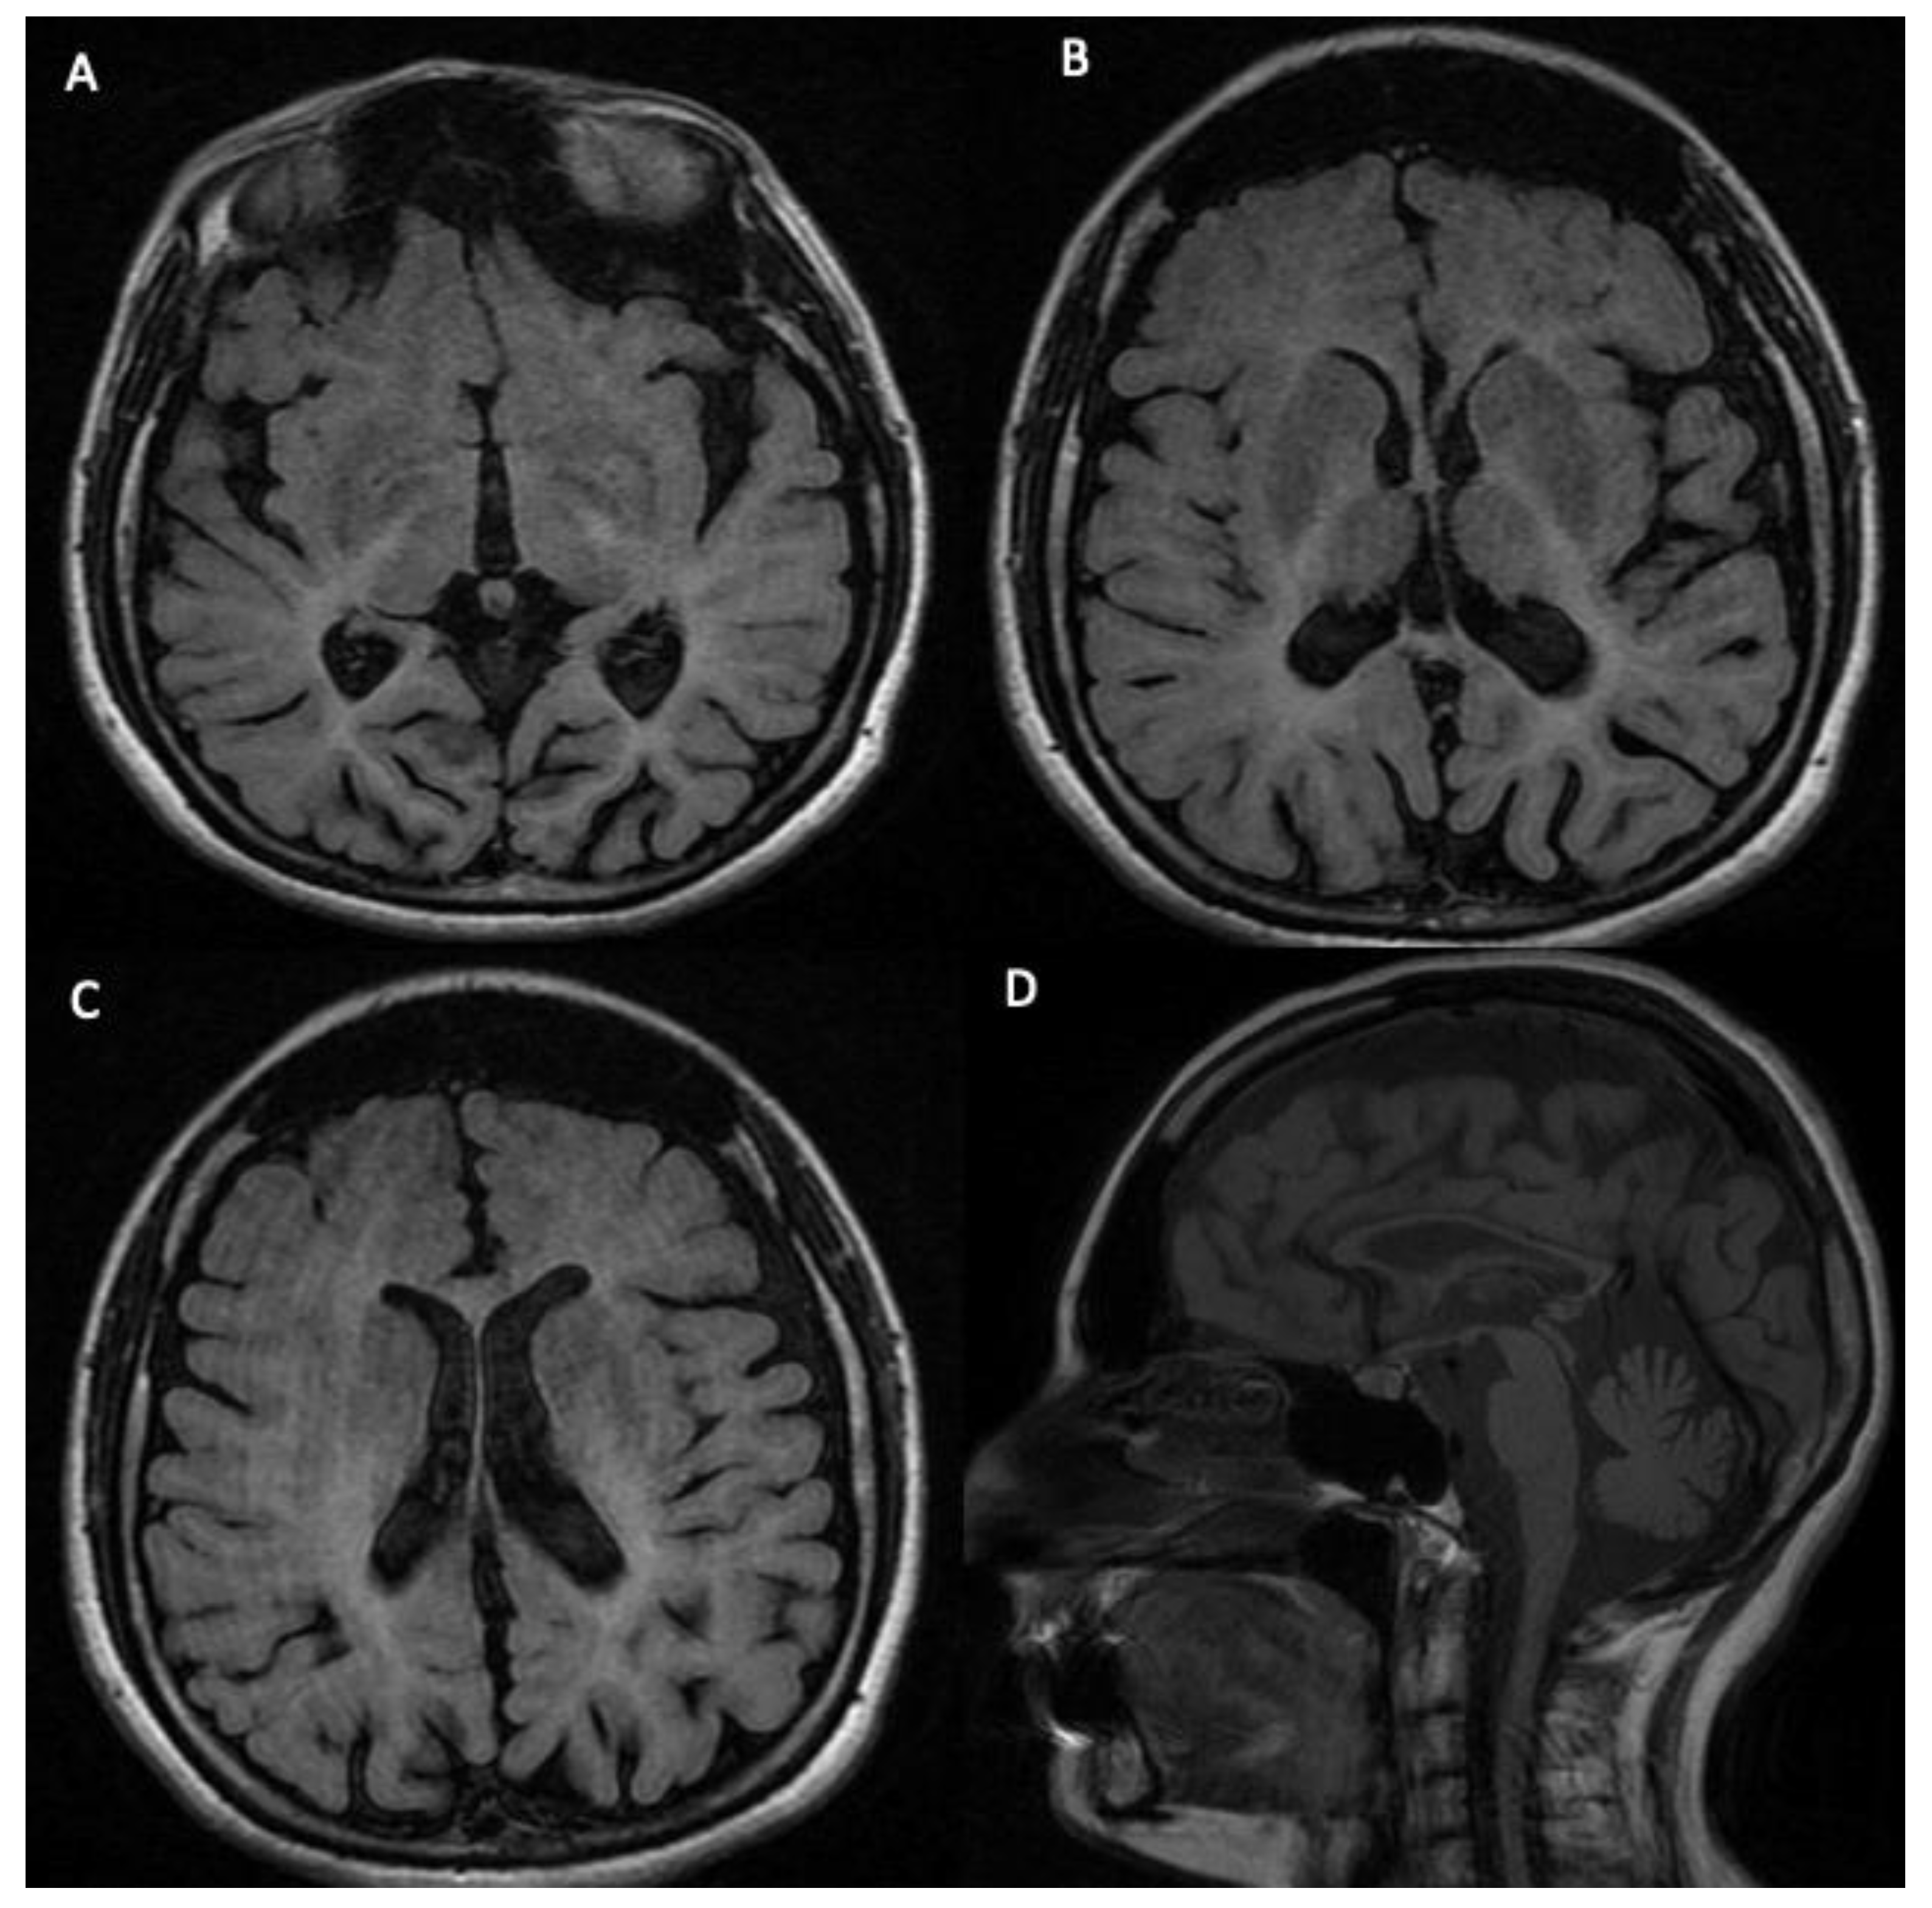

| 4041-NP1139 | 31 | F | Diffuse hypomyelination of the subcortical and deep white matter, enlarged high convexity CSF spaces, ponto-cerebellar hypoplasia, and thin corpus callosum. | Causative mutations |

| 5078-NP1688 | 23 | M | Slight peri- and supra-ventricular white matter hyperintensities and cortical atrophy. | Causative mutations |